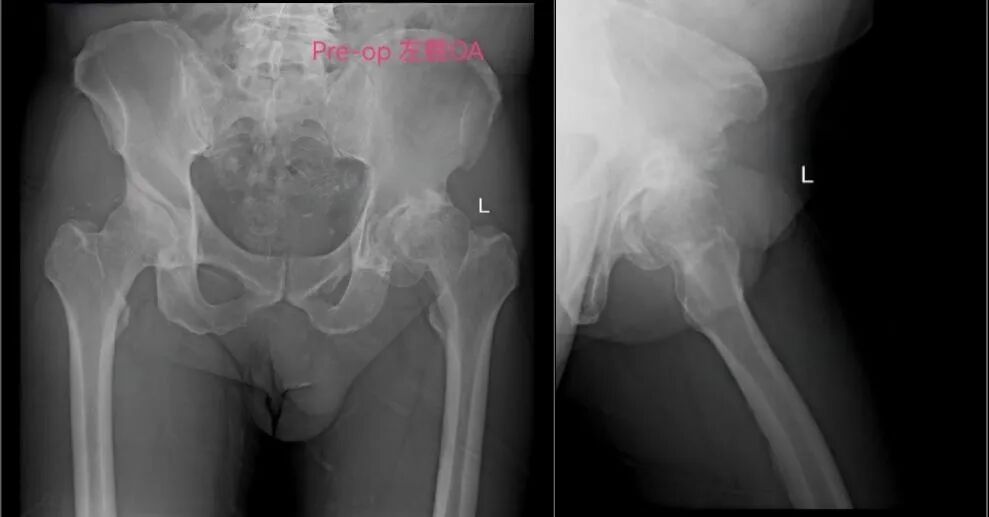

梁大爷多年来饱受左髋关节重度骨性关节炎困扰,行走困难,生活质量严重下降。尽管人工髋关节置换术是有效治疗手段,但因对手术创伤大、恢复慢、风险高的固有印象,手术一直成为他心中的“噩梦”。加上梁大爷有心脏基础疾病,手术与麻醉风险较高,进一步增加了治疗难度。

手术采用微创技术进行全髋关节置换,切口小、组织损伤少、出血量极低,术中无需输血,未留置导尿管,手术时间不足一小时。术后无需拆线、换药,两周后仅需去除伤口敷料即可,极大提升了患者的舒适度和依从性。